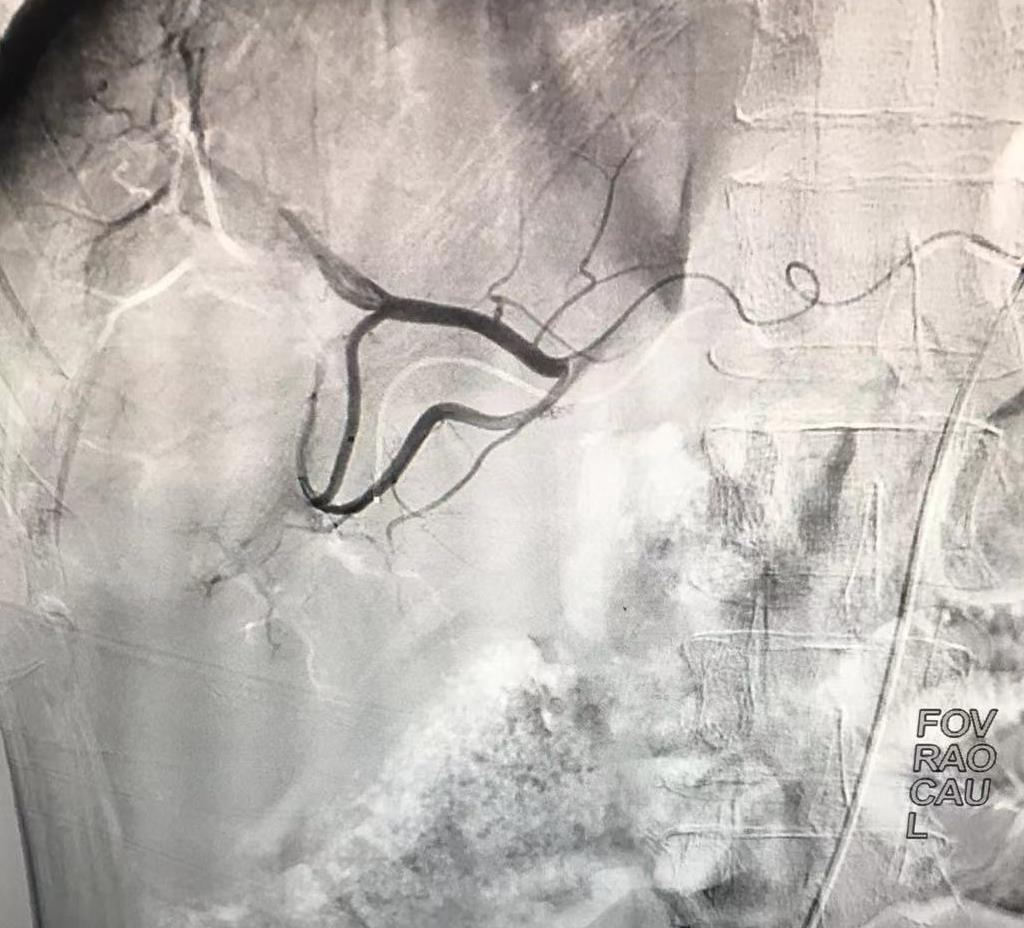

請介入科會診,進(jìn)行術(shù)前病例討論,排除介入禁忌,于5月20日下午15:30為該患者D-TACE+HAIC術(shù),術(shù)中造影發(fā)現(xiàn)患者肝動(dòng)脈畸形扭曲,導(dǎo)絲反復(fù)進(jìn)入肝動(dòng)脈受阻,最后在介入科醫(yī)師的不懈努力下,最終使用微導(dǎo)管超選至腫瘤供血?jiǎng)用},以載藥微球+鹽酸表柔比星60mg栓塞腫瘤供血?jiǎng)用},載藥微球持續(xù)釋放化學(xué)藥物,手術(shù)順利完成。

術(shù)前造影顯示腫瘤由肝動(dòng)脈分支供血,血管增粗屈曲,腫瘤染色顯影明顯。

術(shù)后造影顯示血管栓塞良好,腫瘤未見明顯染色。